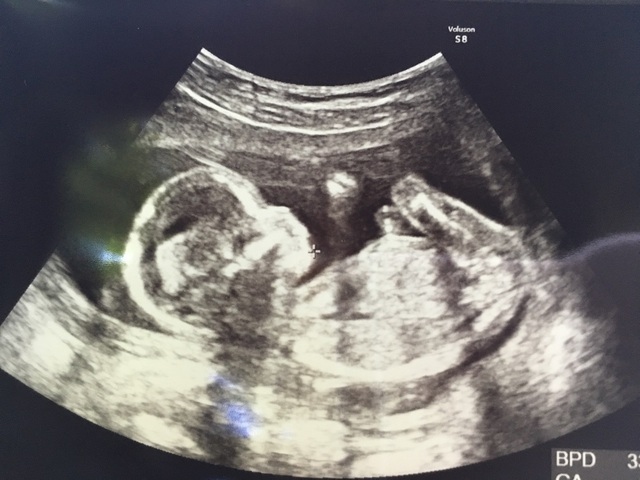

みんなの妊娠17週目のエコー写真をご紹介します。

17週0日(17w0d・男の子)|Ayako. さん(32歳)

エコー写真撮影時のエピソード:

戌の日の安産祈願に行った時に周りの妊婦さんがかなりお腹が大きかったのに、私はお腹がなかなか大きくならずに心配していましたが、エコーの赤ちゃんはきちんと大きくなっていて安心できました。

右手をあげて、こちらに挨拶をしているようなポーズが面白くてお気に入りの一枚です。